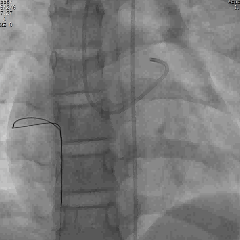

术中封堵前选择性冠脉造影

封堵前造影可见右心房大量造影剂显影